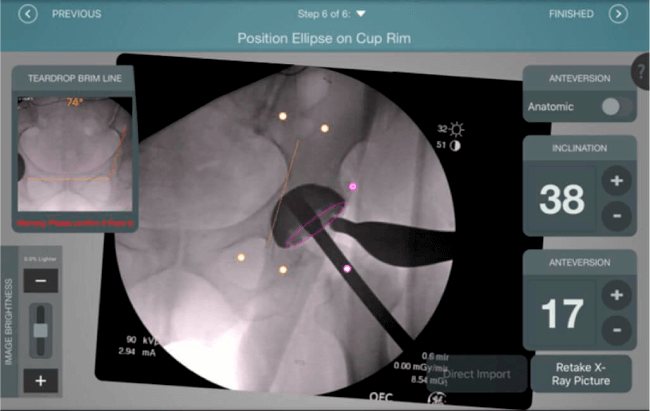

El sistema de navegación digital VELYS HIP NAVIGATION ™ para cirugía de cadera, es una tecnología innovadora y no invasiva diseñada para potencializar la toma de decisiones en tiempo real y basada en datos; aumentando la precisión y mejorando los resultados a corto, mediano y largo plazo para los pacientes.

Planeación preoperatoria mediante la creación de plantillas digitales para reemplazo de cadera y análisis intraoperatorio

Aumenta la precisión y reproducibilidad quirúrgica generando resultados predecibles.

Datos procesables en tiempo real para la toma de decisiones.

Mayor nivel de información intraoperatoria facilita la colocación correcta de los implantes:

Inclinación y anteversión de la copa acetabular para una correcta colocación del implante.

Verificación de la posición deseada del implante que potencialmente puede ayudar a reducir la probabilidad de dislocación protésica y aumentar la estabilidad de la articulación.